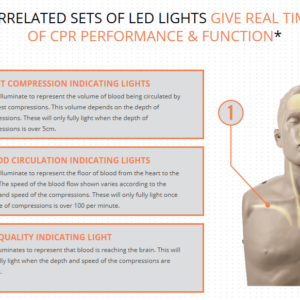

Brayden Baby Advanced

- Brayden Baby allows the correct compression depth of at least a 1/3rd of the AP distance of manikin (4cm).